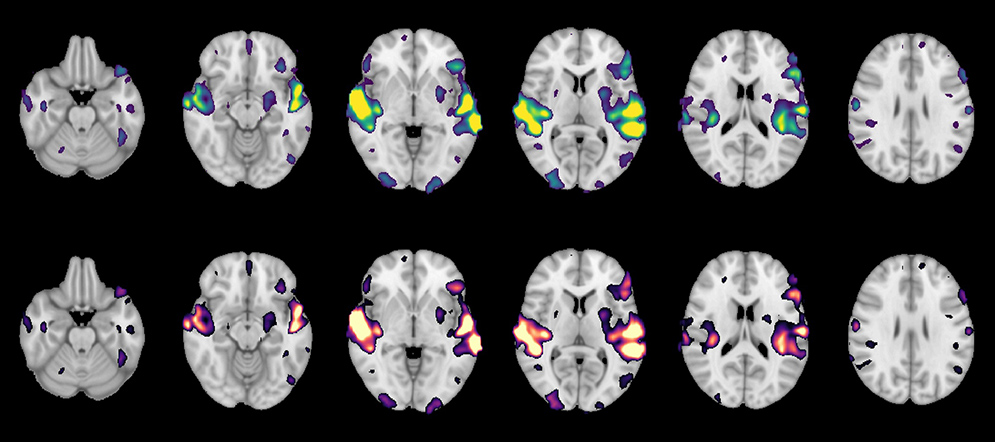

Sam Ling, a CAS assistant professor of psychological and brain sciences, has been using the scanner to carry out research funded by the National Institutes of Health aimed at “understanding how our brains process what we see and the neural computations that allow us to alter that processing to cater to our moment-to-moment thoughts and desires,” Ling says.

“Our lab has totally embraced the scanner,” he says. “The quality of the data we’ve been acquiring is outstanding. We’re already starting to write up manuscripts based on some of the results.”

Perrachione explains how the CNC’s scanner benefits his research. “First, it has a great signal-to-noise ratio, meaning that we can see the living, thinking brain in unprecedented detail,” he says. “Second, it has a new technology called simultaneous multislice imaging, which is a fancy way of saying we can take an fMRI picture really, really fast—up to four times faster than we used to. This means we can do scans that are quieter and get a lot more data in the same amount of time, which is really important when you’re studying speech and hearing. Getting a lot more data in each scan means we can better understand how individual brains are working, rather than having to get an average of a lot of brains. This will help us develop a more personalized and sensitive understanding of brain function and its relationship to behavior and health.